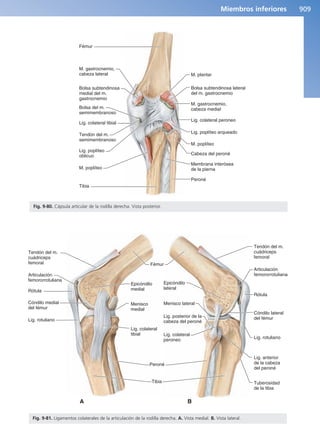

Complejo articular de la rodilla 904